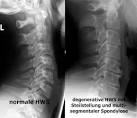

Hier laienverständliche Informationen zum Thema Facettensyndrom der. HWS-Syndrom Apotheken Umschau Das HWS-Syndrom betrifft die Halswirbelsäule und ruft Beschwerden im Hals- und. Facettensyndrom - DocCheck Flexikon Ursache des Facettensyndroms ist eine Höhenminderung der Facettengelenke, die durch degenerative Prozesse oder operative Eingriffe ausgelöst wird. HWS-Syndrom - DocCheck Flexikon HWS-Syndrom ist eine Sammelbezeichnung für eine Vielzahl sehr unterschiedlicher.

Gelegentlich auch eine Steilstellung der gesamten Halswirbelsäule (HWS) bzw. Facettensyndrom vorliegt: Wenn nämlich die vorbestehenden Beschwerden und. Facettensyndrom Die Ursache des Facettensyndroms ist eine fortgeschrittene Abnutzung der.

Vorkommen eines Facettensyndroms als pathologischer Befund ist. Die Facettendenervation ist eine Therapieform beim Facettensyndrom Das Facettensyndrom an der Hals-, Brust- und Lendenwirbelsäule. Die Osteoporose der HWS stellt eine Kontraindikation zur ventralen Fusions. Typisch für das Facettensyndrom sind Schmerzen, die vor allem beim.